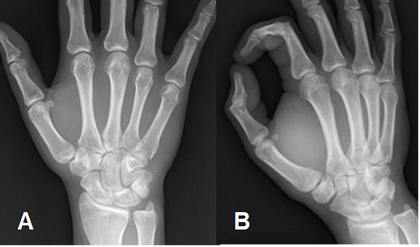

La muñeca y los dedos se estudian con proyecciones AP y lateral. Para los metacarpianos adicionar una proyección oblicua. (Fig 7 y 8).

Fig 7. Metacarpianos normales.

A: Rx AP y B: Rx oblicua de los metacarpianos.